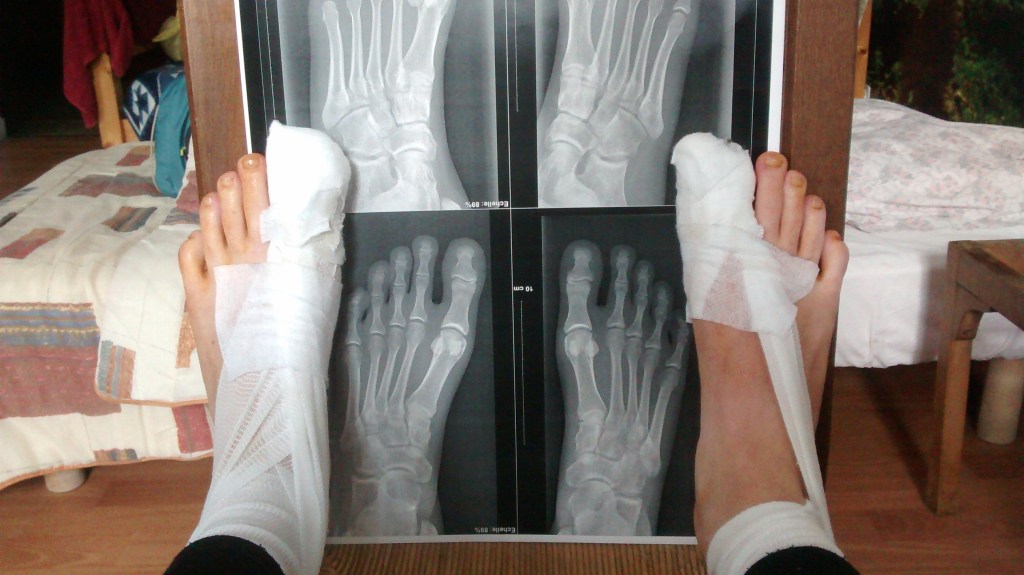

My foot surgery: a cautionary tale

This is a bit graphic, but you’d better get used to it now; foot stuff is 80% of what pilgrims talk about.

In 2016, I bought shoes that were slightly too small and completely waterproof, which led to crushed toes and endless blisters. By my second week, both of my big toenails had died. They didn’t fall off right away, and the added friction led to infected blisters trapped underneath.

I ignored the pain for weeks until, finally, an extremely generous local woman saw how much danger I was in and drove me to the hospital. My ignorance and stubbornness led to surgery and a 2-week hiatus from my Camino. Had I ignored the infections any longer, they would have spread to my bones and I would have lost my toes.

It was an expensive, time-consuming, and painful error… Don’t make my mistakes!